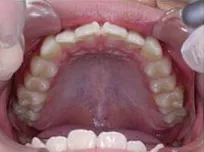

症例1

| 治療期間 | 11ヶ月(2021年6月〜2022年5月) |

| 費用 | 495,000円(税込) |

| リスクや副作用 | 成長期が終わった18歳以降に、2期矯正が必要になることがある |